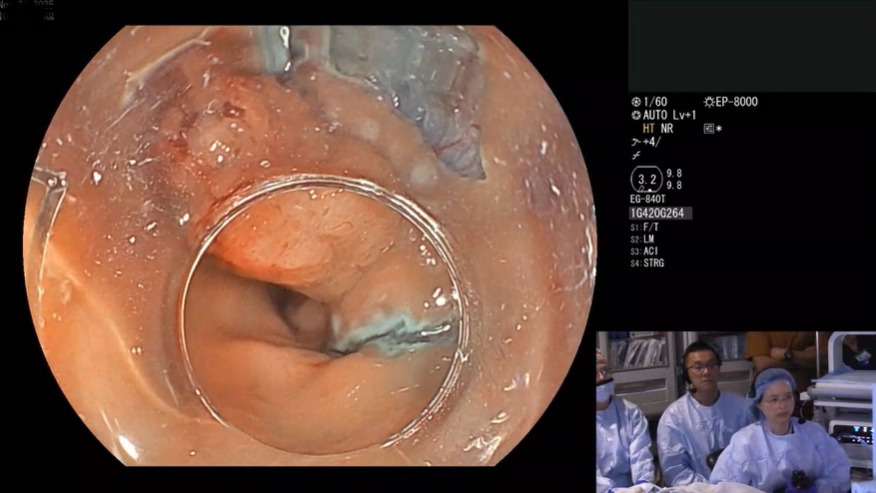

Through real-time case demonstrations and expert-led discussion, this program will explore a range of closure strategies across EMR, ESD, POEM, and fistula management. Emphasis is placed on technical decision-making, device selection, and procedural nuances to support safe and effective defect closure in everyday clinical practice.

Case 1: EMR Clip Closure

Case 2: EMR Clip Closure

Case 3: Closure of EMR Defect – Suture Closure

Case 4: POEM Closure

Case 5: Closure of ESD Defect

Case 6: PEG Fistula Ablation/Closure

Case 7: GG Fistula Ablation/Closure